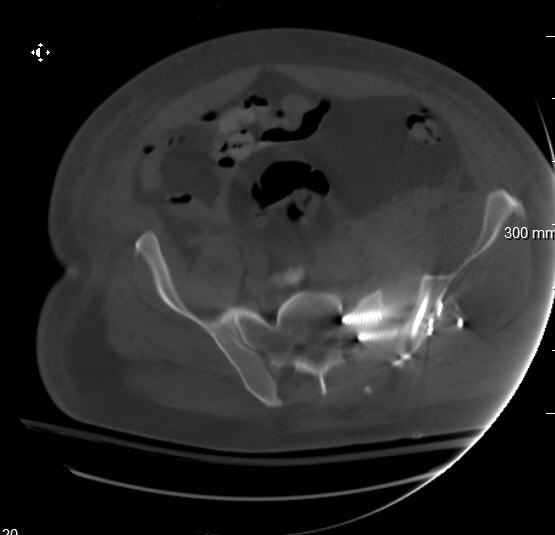

Hello gentlemen- Case is 52 YO male, fell out of treestand while deerhunting. He is 6 ft, approx. 260-275 lbs. Was hemodynamic unstable at local ER, sent to our Trauma center where circumferential pelvic binder placed and pt. stabilized with fluid, blood, and rewarming. Angiography not performed. An extraperitoneal bladder disruption was found, uro elected to treat non-operatively. Initial xray (not shown) demonstrated 5-7 cm wide at symphysis and SI joint. The first image attached is of CT once binder is in place. On post trauma day 5 the pt was taken to OR for ORIF of his iliac wing fracture and SI dislocation. The swelling/3rd spacing of fluid in the area of symphysis was profound, but quite acceptable posteriorly. Patient was prone for procedure, as I thought too difficult to fix the wing in lateral position. Of course the repair of wing was easy, but reduction of SI very demanding. The Floro images document the residual lack of reduction. That was the closest I could get it using 6mm joystick in wing, and clamp on sacrum and clamp through notch. The fixation was (initially) rigid. Anterior ex fix with supra-acetabular pins was placed due to condition of soft tissues, massive "beer-belly" overhanging the crest. Post trauma day ten patient's xray shows failure of posterior construct. Plan was to perform revision orif once soft tissues resolve considerably for full anrterior fixation and posterior fixation. However, while Im away for holiday (on Post trauma day 15), pt is developing septic clinical appearance, and trauma suspects pelvic abcess near symphysis and performs I and D - finds nothing but no primary closure performed. Posterior tissues/incision continue to look healthy. Now is post trauma day 17, pt is still tubed/on dopamine/and wbc still elevated, anterior incision still packed open. Clearly must get to bottom of possible sepsis, but then what? Thanks for you time - sorry for such lengthy clinical description. Thomas Schaller Kalamazoo, Michigan

5. Your caudal iliosacral screw is/was in his spinal canal... it's low and posterior and the lateral fluoro image confirms this... a postop CT will show it (or it's trail at this point)... canal screws do not hold.

My plan to revise fixation is in line with your suggestion - plate symphysis and anterior approach to SI joint. It appears from post - failure CT scan that the path of the more cephalad IS screw may be helpful to place a longer screw to engage opposite illiac wing as an option, or just anterior SI plates. not likely to do this tomorrow as he remains in a fragile clinical situation regarding his pulmonary status, and profound edema/induration around his pelvis/abdomen and thighs.